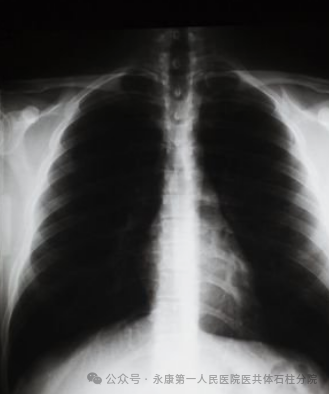

X线成像就是大家常说的“拍片”。X线具有一定的穿透性,人体各部的组织结构之间存在着固有的密度和厚度差异。当X线穿透人体组织时,会发生不同程度的吸收,高密度组织如骨骼对X线吸收多,透过的X线少,所以在X线片上大家看到的肋骨、股骨、腓骨等骨骼呈白影;低密度组织如含气的肺,就与之相反,对X线吸收少,透过的多,呈黑影;中等密度组织如实质器官,介于前两者之间,呈灰影。

(2)X线摄影也饱受儿科医生的青睐。在儿科,很多咳嗽、痰多、发烧的患儿,也经常会收到一张胸片检查单。胸片可以支持肺炎的进一步诊断,肺炎是由于各种病原菌侵袭肺组织,出现充血、水肿、炎症性浸润。炎症的病灶在胸片上表现为片状、点状或者是斑片状的密度增高影。医生通过胸片,可以判断患者是否患有肺炎、支气管炎、脓胸、气胸、胸腔积液等疾病。